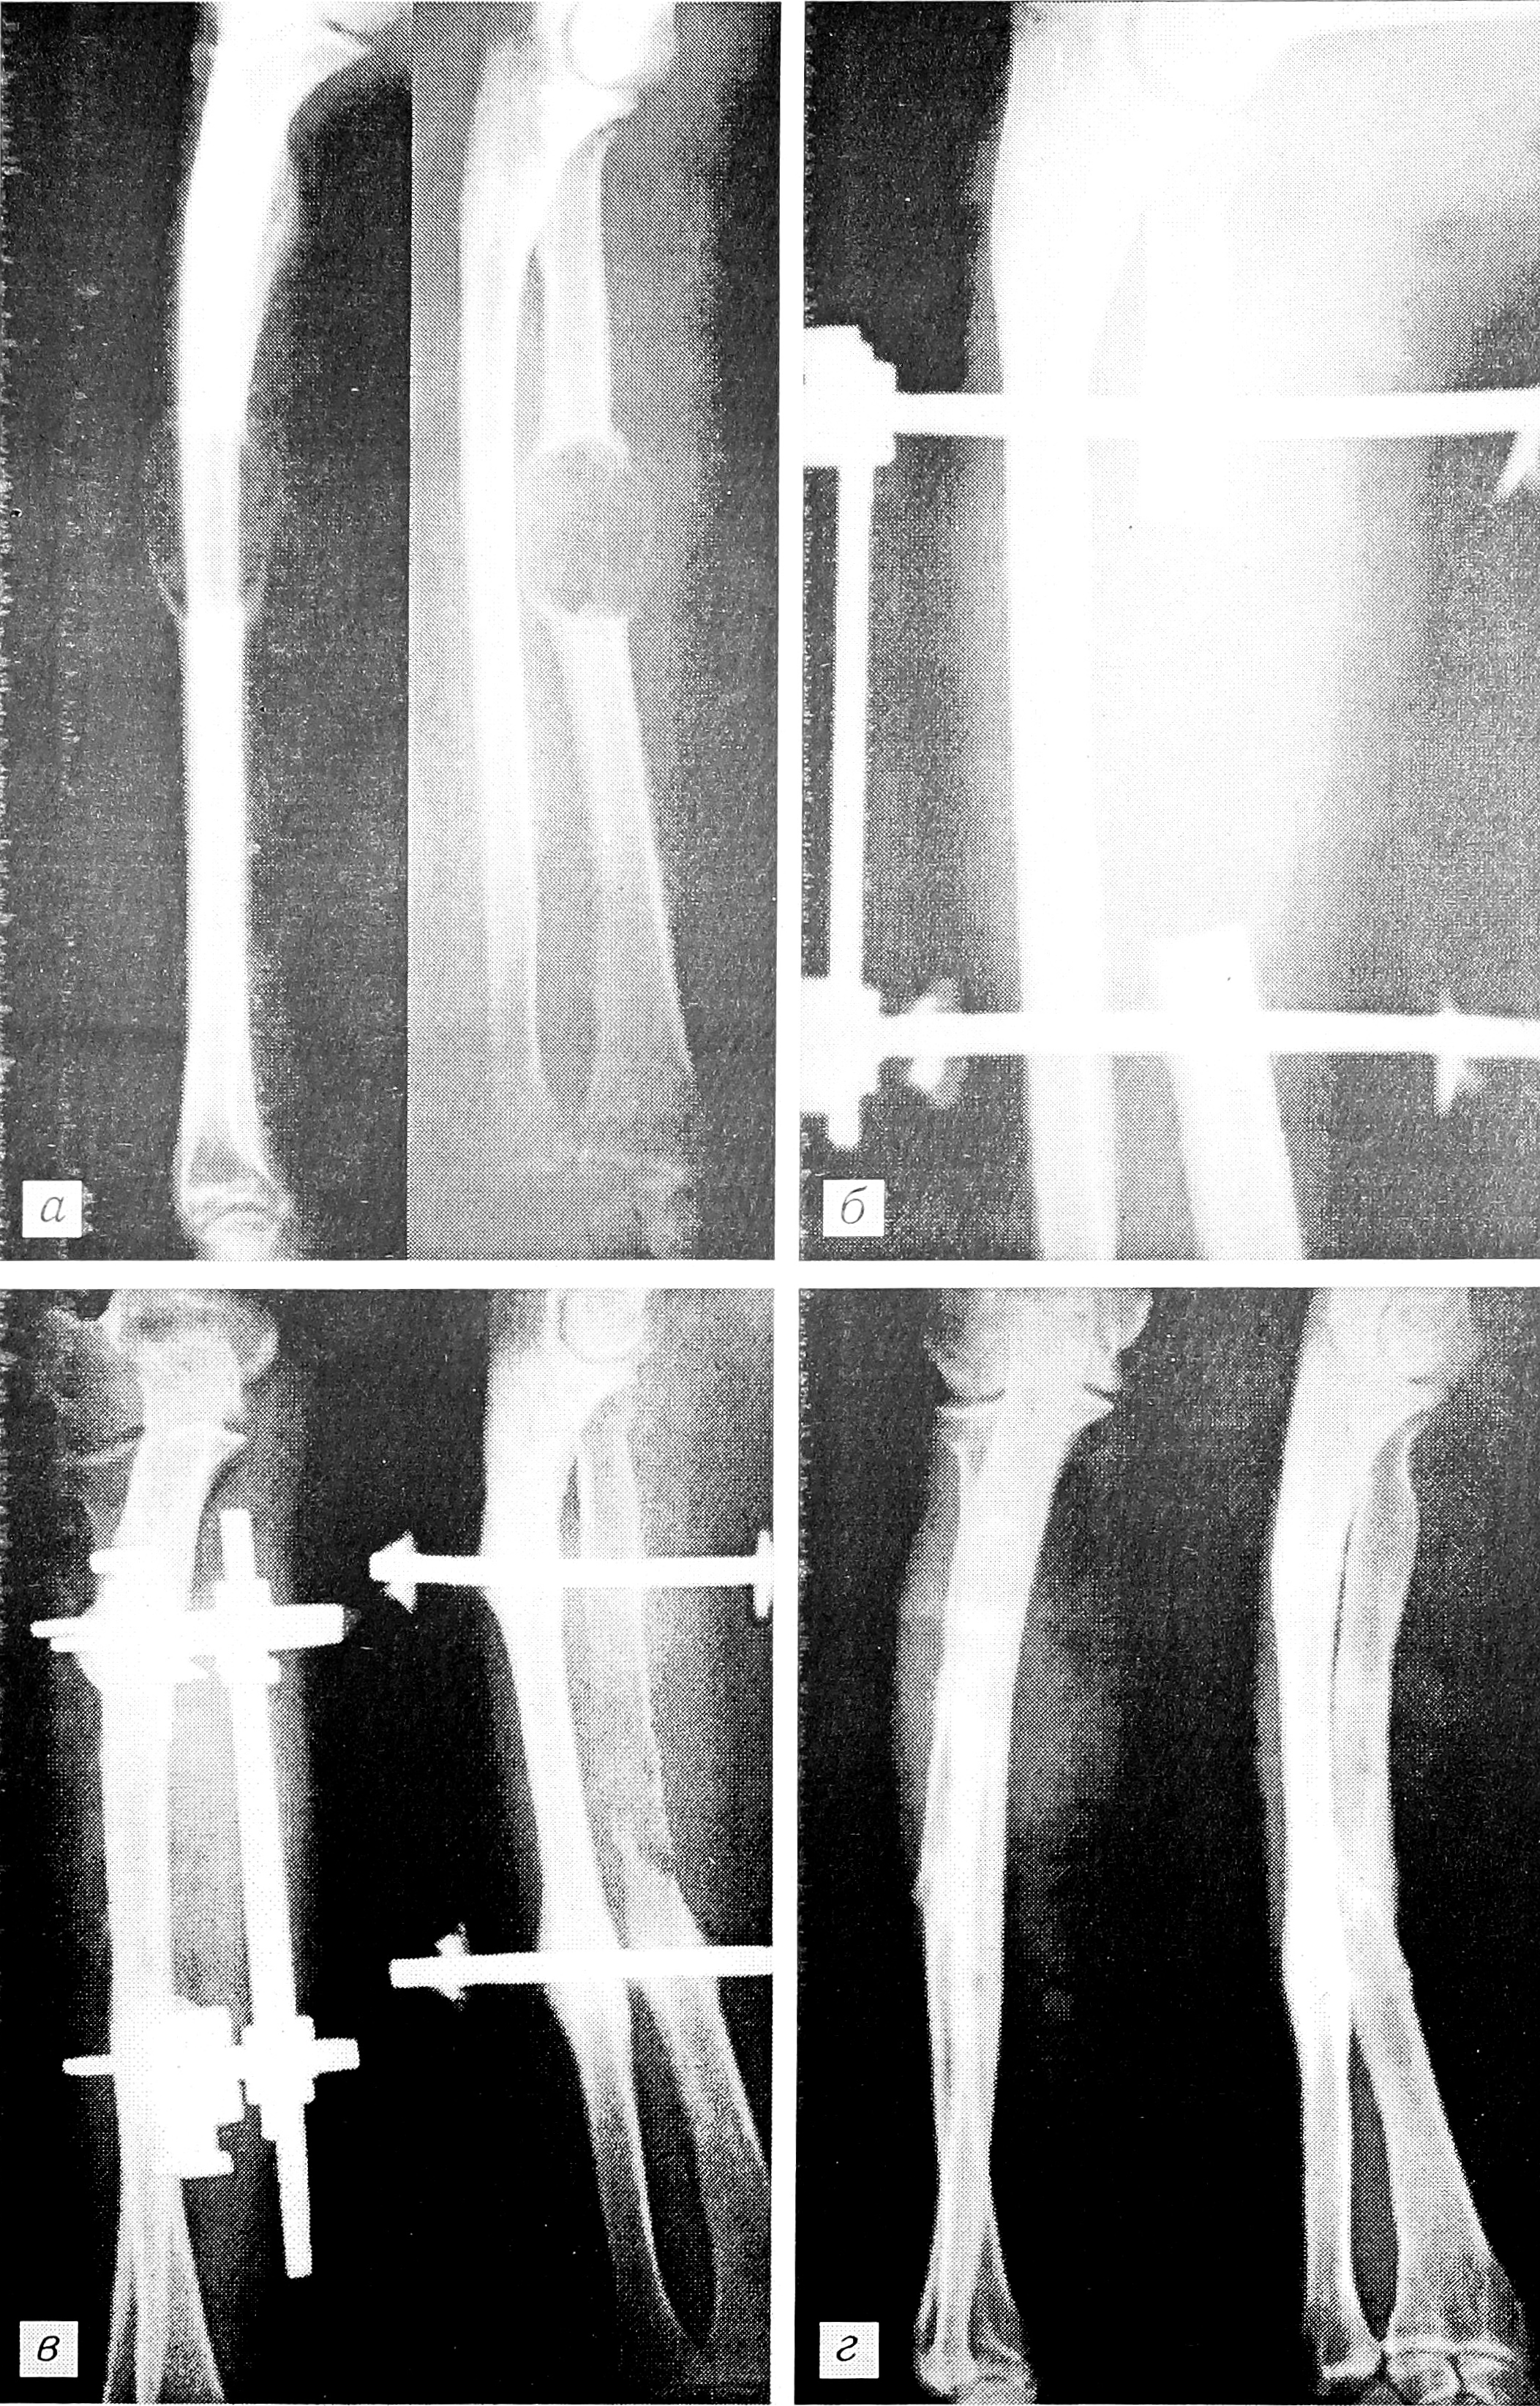

Рис. 2. Рентгенограммы больного с гигантоклеточной опухолью лучевой кости.

а — до операции, б — после выполнения сегментарной резекции с наложением аппарата Илизарова и замещением дефекта аллогенным костным матриксом, в — через 6 мес, г — через 1,5 года после операции.